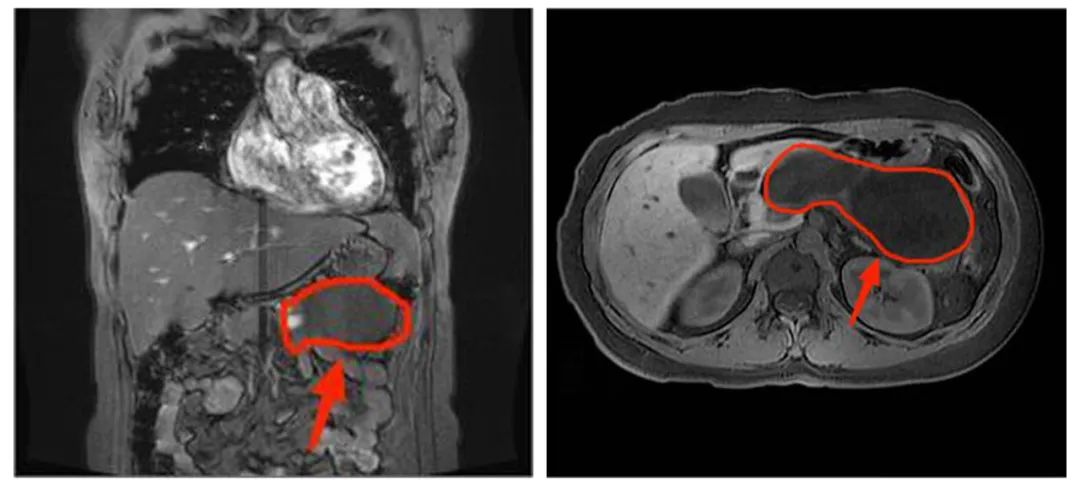

一名34岁女性患者,因“孕15周,腹胀1月余、伴腹痛4天”入院。经核磁共振检查发现胰腺体尾部有一大小约124mm×58mm×56mm的巨大囊性占位性病变。因患者胰腺病灶性质不明,不排除恶性可能,且病灶巨大、已有压迫症状,并随着孕周增加有进一步增大、胰腺炎发作、病灶破裂出血等风险。经普通外科、产科、麻醉科、影像科等多学科会诊后建议手术切除。

术前影像学检查